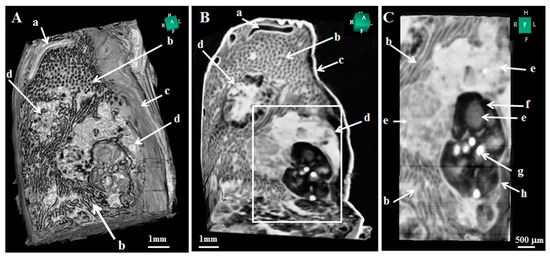

- Wu, J.; Takeda, T.; Lwin, T.T.; Momose, A.; Sunaguchi, N.; Fukami, T.; Yuasa, T.; Akatsuka, T. Imaging renal structures by X-ray phase-contrast microtomography. Kidney Int. 2009, 75, 945–951. [Google Scholar] [CrossRef]